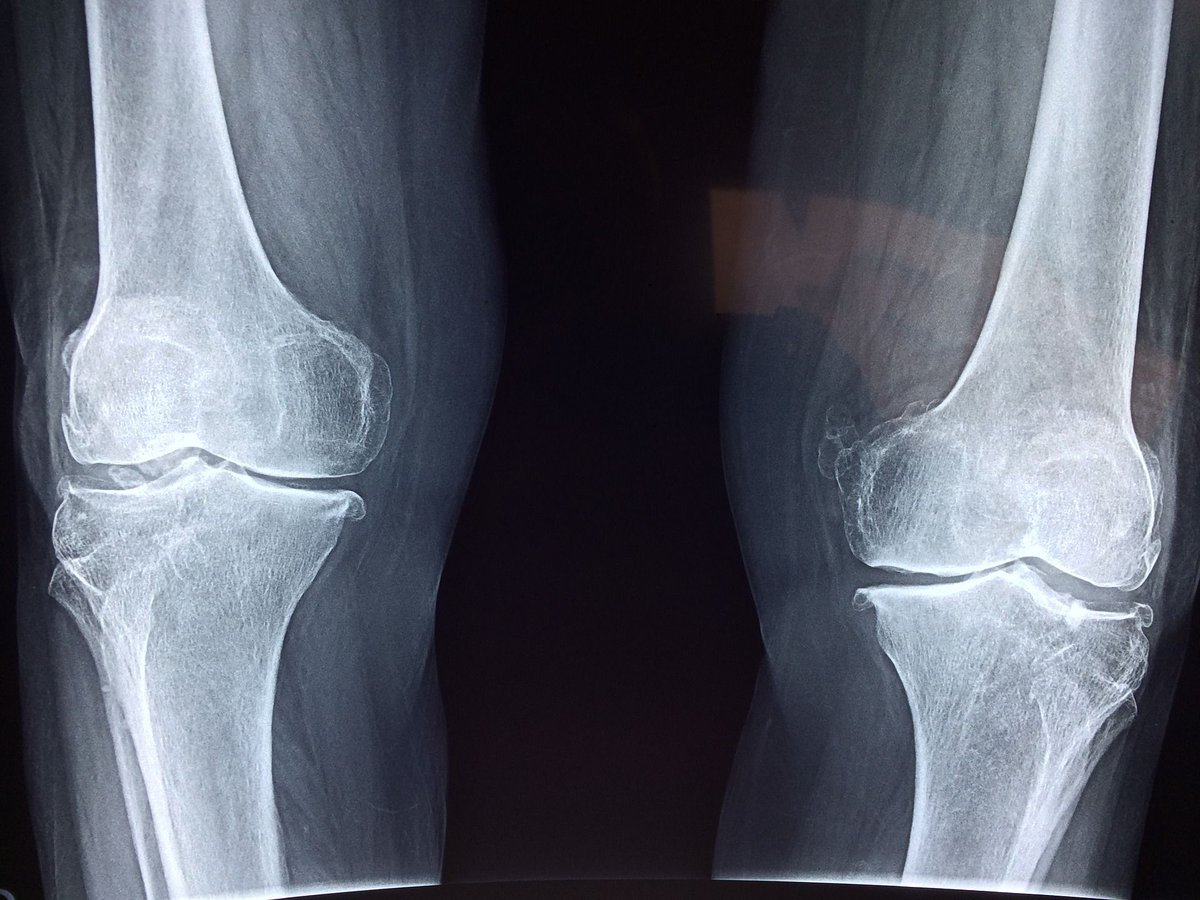

Recent research and publications have underscored the use, efficacy, safety and limitations to the use of cannabis for arthritis and pain patients.